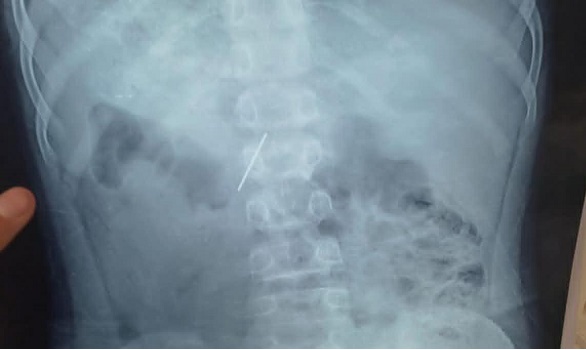

في إنجاز طبي جديد، نجح قسم جراحة الأطفال بمستشفى الأطفال التخصصي ببنها في إنقاذ حياة طفل بعد استخراج مسمار دباسة كراسة اخترق جدار البطن واستقر داخل التجويف البطني، وذلك عبر تدخل جراحي متقدم جمع بين المنظار الجراحي وتقنية جهاز السي أرم لتحديد الموقع بدقة متناهية.

وصل الطفل إلى المستشفى وهو يعاني من آلام شديدة أقلقت أسرته، وكشفت الفحوصات الأولية عن وجود جسم معدني حاد داخل البطن. وبناءاً على النتائج، قرر الفريق الطبي التدخل الفوري لاستئصال المسمار بأسرع وأأمن طريقة ممكنة، حفاظاً على حياة الطفل وتفادياً لأي مضاعفات خطيرة.

استخدم الفريق المنظار الجراحي لتقليل آثار العملية وتسريع الشفاء، بينما ساعد جهاز السي أرم في تحديد موقع المسمار داخل البطن بدقة مذهلة، ليكون دليلاً حيويًا للجراحين في كل خطوة، ما حوّل العملية إلى مثال حي على تكامل مهارة الإنسان مع ذكاء الآلة.